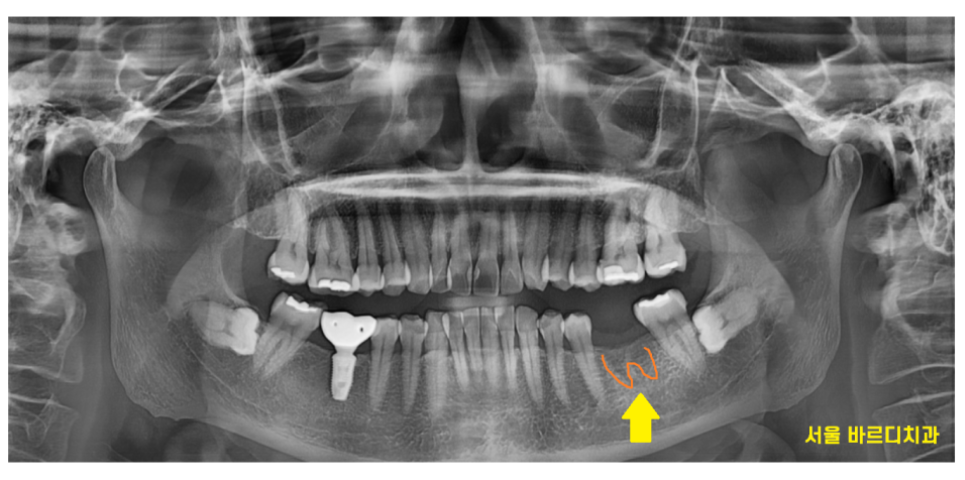

사진을 보시면 아시겠지만

일반적으로 임플란트 크라운 크기

자연치에 비하여 작게 느껴지실텐데요.

실제로도 작게 만들어드립니다.

23.12.19

일반적으로 어금니를 막 뽑은 상태면

뿌리 형태가 남아있습니다.

어금니의 뿌리는 3-4개 정도 되는데요.

그렇지만 임플란트는 뿌리가 따로 없죠?

임플란트는 1개로 들어가게 됩니다.

24.01.11

위에 사진처럼 말이죠.

임플란트의 폭경

그러니까 가로 넓이가

일반 치아에 비하여

작습니다.